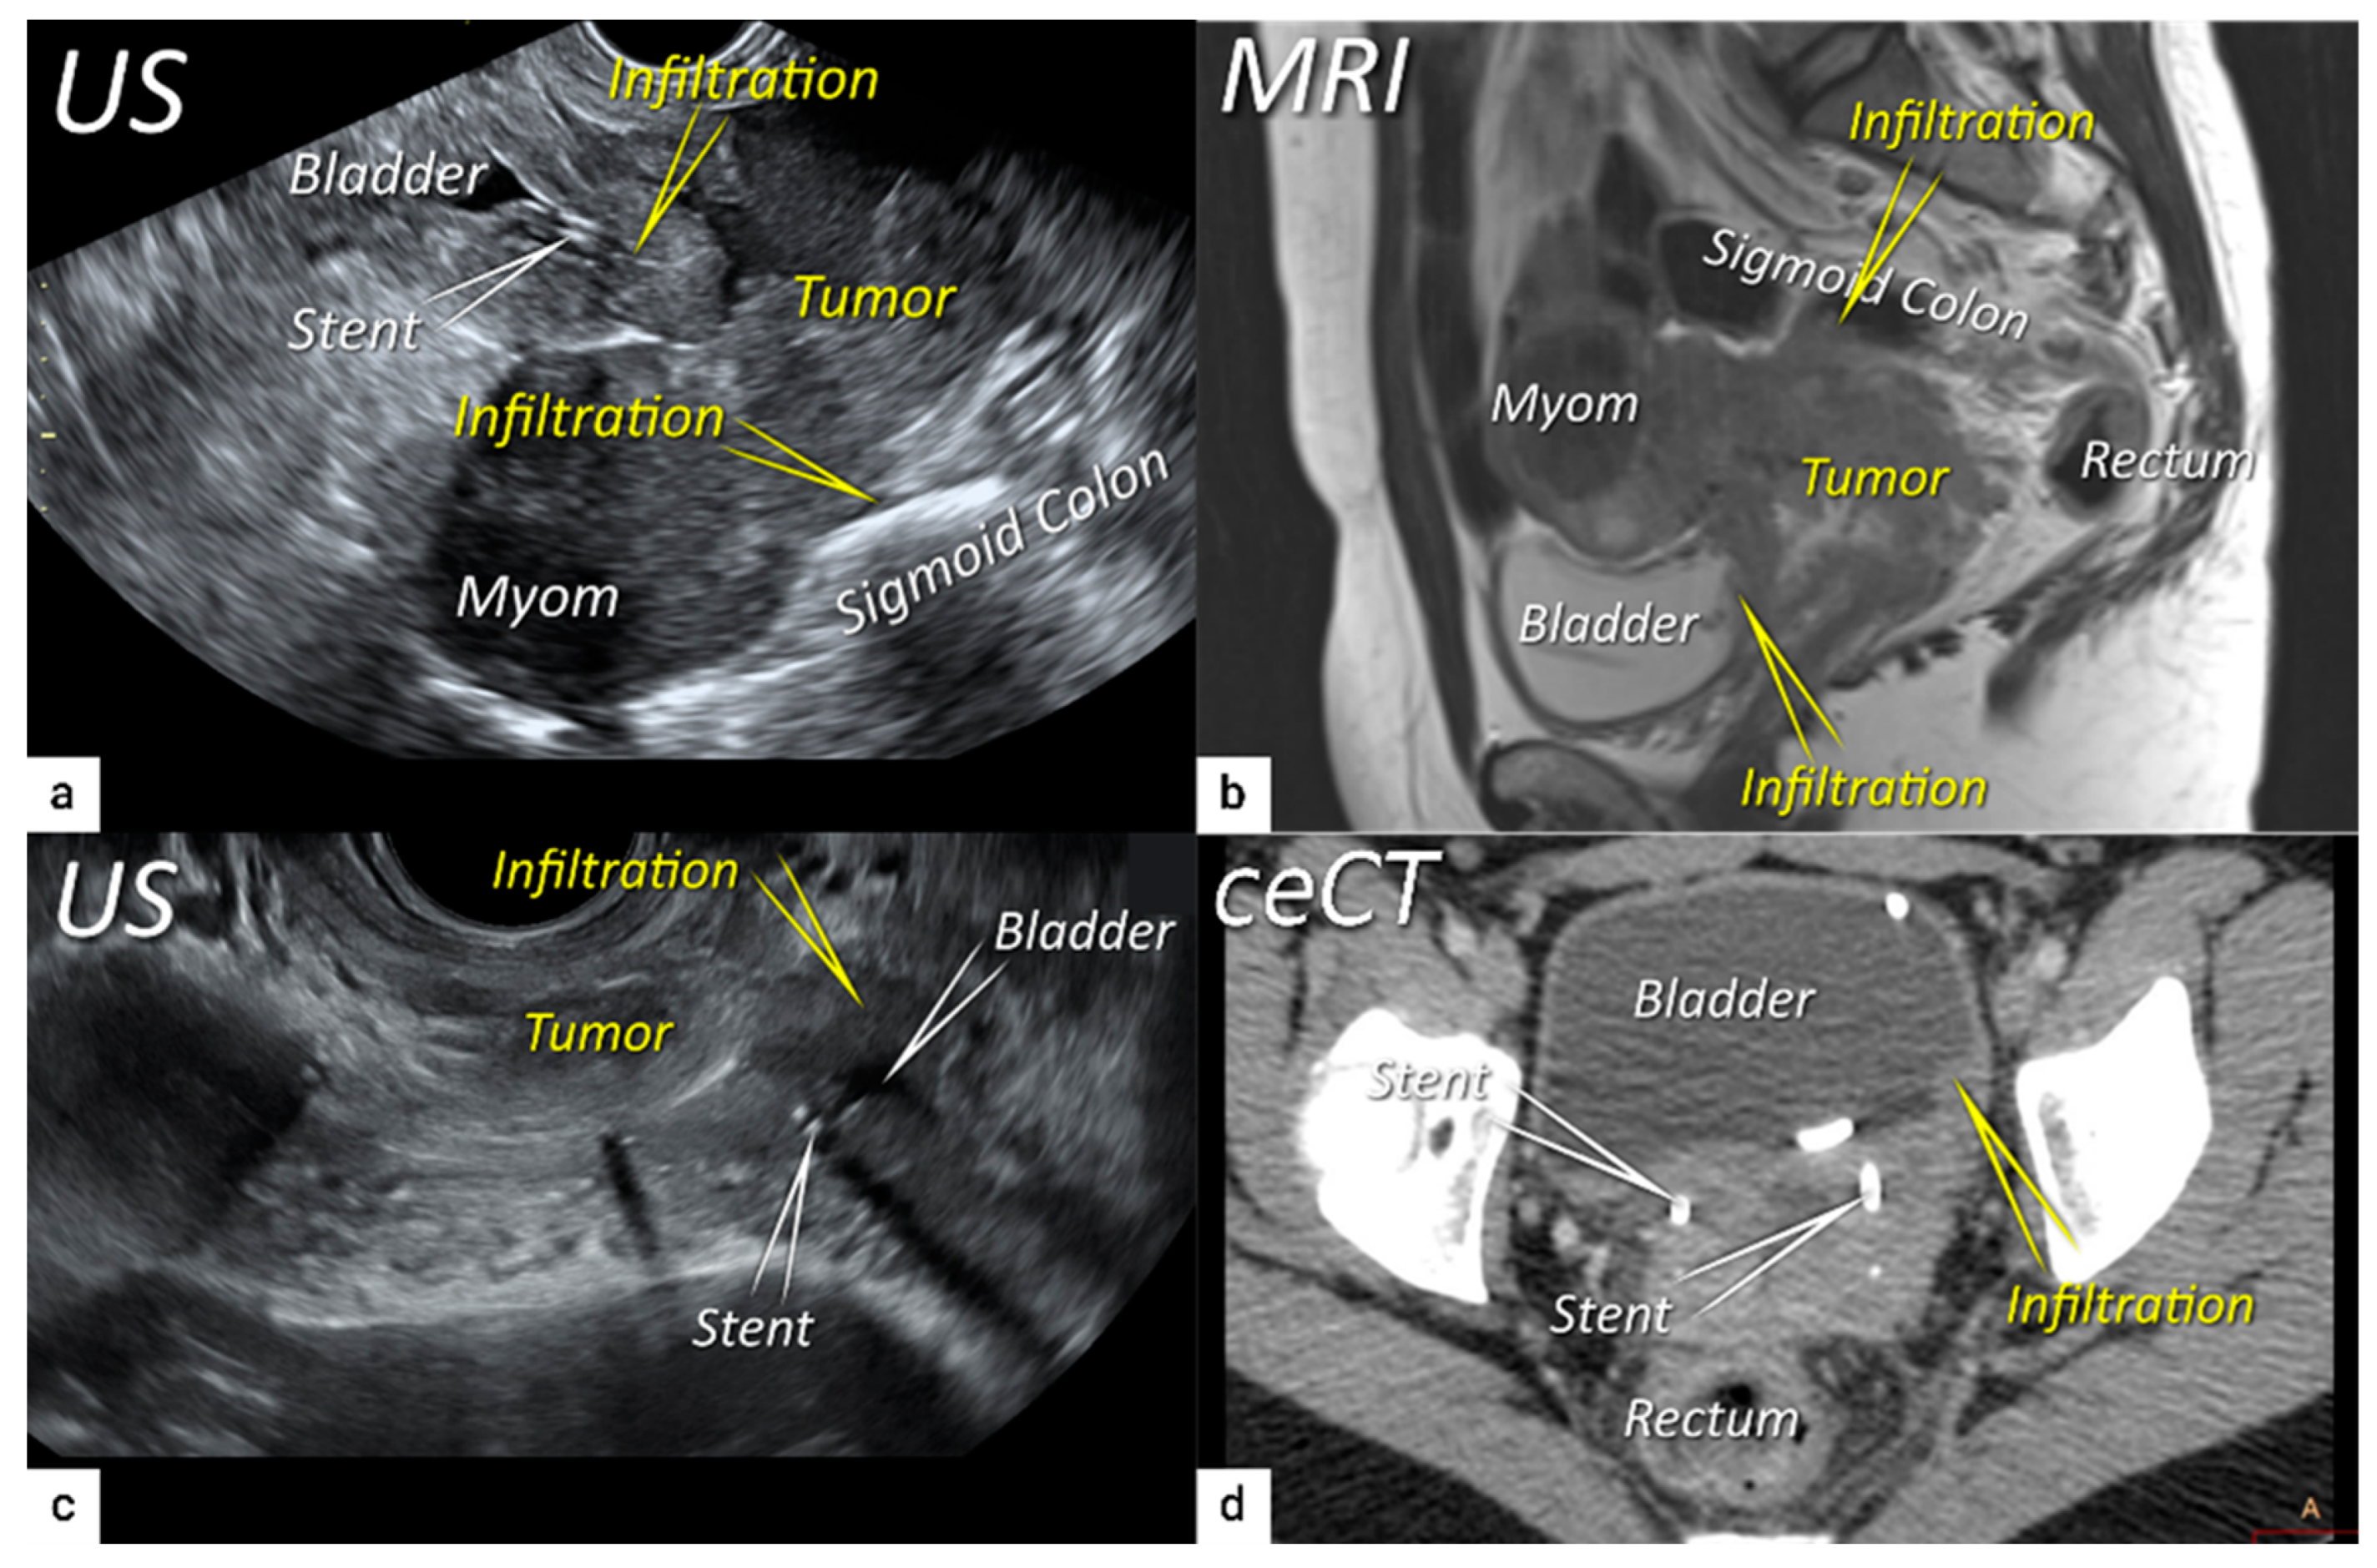

| T4f | IVAf | Tumour invasion into the mucosa of the bladder or rectum (biopsy-proven) or into adjacent organs. | US: Negative sliding sign, hypoechogenic tumour infiltration of bladder / rectal wall up to echogenic mucosa with polypoid tumor seen intraluminally. MRI: Focal or diffuse disruption of the normal T2-low signal intensity wall of the bladder/rectum, irregular or nodular wall, sometimes including an intraluminal tumour mass. Bulous edema sign, which is hyperintense thickening of the bladder mucosa on T2W images, is only an indirect sign of invasion and should not be regarded as T4 unless confirmed mucosal infiltration at cystoscopy. Infiltration of the posterior bladder wall without mucosal infiltration should not be regarded as T4a. |

3.4. Extension to surrounding organs (bladder, rectum, sigmoid colon)